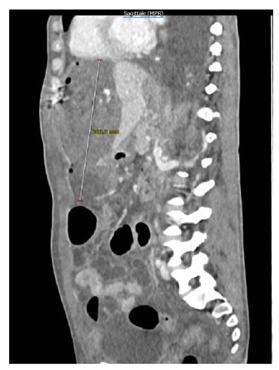

Hemoperitoneum often occurs due to abdominal trauma, abdominal tumors, gastro-intestinal perforation and more rarely it's spontaneous due to coagulopathies. Superior epigastric artery (SEA) iatrogenic damage is rarer than the Inferior epigastric artery injury, it may occur during laparotomy and, in most cases, it causes a rectus muscle hematoma. We present the case of a caucasian 44 years-old-woman with hemoperitoneum after cytoreductive surgery for ovarian cancer. Active bleeding from the distal branch of the SEA was diagnosed at computed tomography and coil embolization followed by surgical laparotomic drainage of the hemoperitoneum was performed. After initial resolution, active bleeding from the same vessel was observed. Further embolization of the same vessel was necessary to stop bleeding. Ultrasound follow-up showed a complete resolution of the hemoperitoneum.

腹腔积血通常由于腹部创伤、腹部肿瘤、胃肠穿孔等引起,极少见情况下也可能由于凝血功能障碍而自发性发生。胃网膜上动脉(SEA)医源性损伤比腹壁下动脉损伤更为罕见,它可能发生在剖腹手术中,且大多数情况下会导致腹直肌血肿。我们报告了一例 44 岁白人女性,在卵巢癌减瘤手术后发生腹腔积血。CT 诊断为 SEA 远端分支出血,随后进行了血管内弹簧圈栓塞治疗,接着进行了剖腹手术引流腹腔积血。最初积血得到控制后,再次观察到同一血管的活动性出血。需要进一步栓塞同一血管以止血。超声随访显示腹腔积血完全吸收。